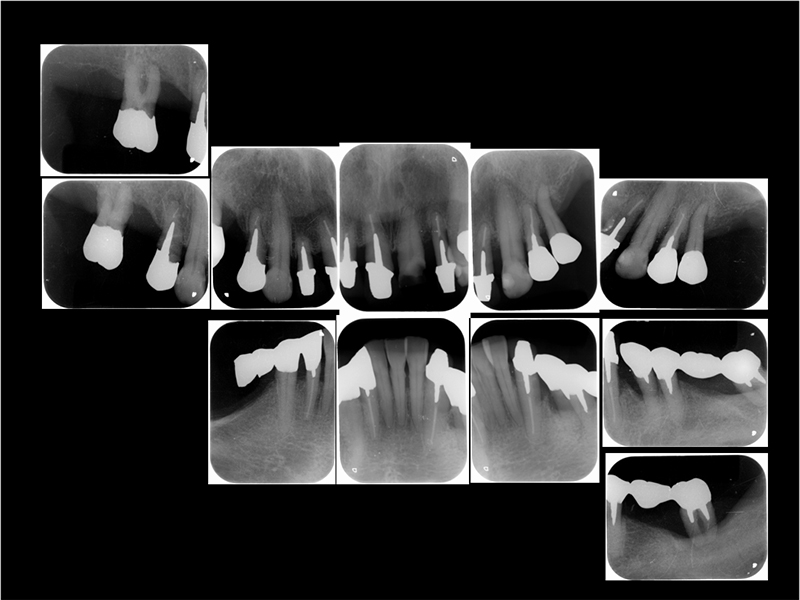

治療前X線写真